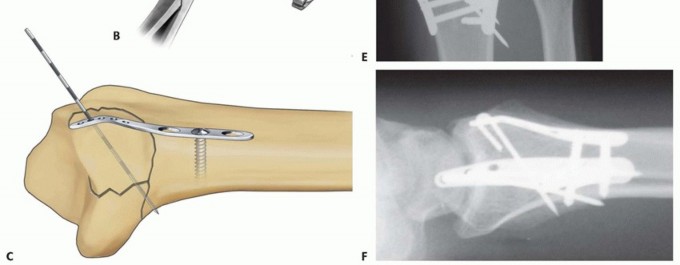

ULNAR PIN PLATE

TECH FIG 10 • Ulnar corner fixation with an ulnar pin plate. A. Insertion of the interfragmentary Kirschner wire. B. Contouring the plate. C. Application of the plate and insertion of the initial fixation screw. D. Fixation completed. E,F. Radial and ulnar pin plate fixation of a three-part articular pattern (radial column and ulnar corner fragment). Slide the plate over the Kirschner wire and fix it proximally with a 2.3-mm bone screw ( TECH FIG 10C).Insert a second Kirschner wire if the fragment is large enough. Create and impact hooks as described for the radial pin plate ( TECH FIG 10D-F).If the Kirschner wire tips protrude beyond the volar cortex, they can be cut flush to the bone surface through a volar incision.

DORSAL BUTTRESS PIN

TECH FIG 11 • Dorsal buttress pin fixation. A. The position of the Kirschner wires is checked with a Carm before inserting the implant. B. Placing an implant upside-down on bone to template the trajectory of the Kirschner wires. C. Inserting the dorsal buttress pin. D. Buttress pin fixation completed. E,F. Fixation of a three-part articular fracture with radial column and ulnar corner fragment with radial column plate and dorsal buttress pin. Ensure that the leading tips of the legs of the dorsal buttress pin are straight and cut to the required length. Leave the ulnar leg 2 to 3 mm longer than the radial leg so one leg can be engaged at a time. Direct the legs proximally if needed to match the insertion angle of the Kirschner wires.Place the ulnar leg of the buttress pin adjacent to the insertion site of the ulnar Kirschner wire, and then withdraw the Kirschner wire and immediately engage the leg in the hole ( TECH FIG 11C). Repeat with the radial Kirschner wire to engage the radial leg of the buttress pin. Impact and seat the buttress pin (TECH FIG 11D).Fine-tune the reduction and complete the fixation proximally with one or two 2.3-mm cortical bone screws and washers ( TECH FIG 11E,F). If needed, a blocking screw can be placed just proximal to the end of the buttress pin to prevent shortening of the fragment.